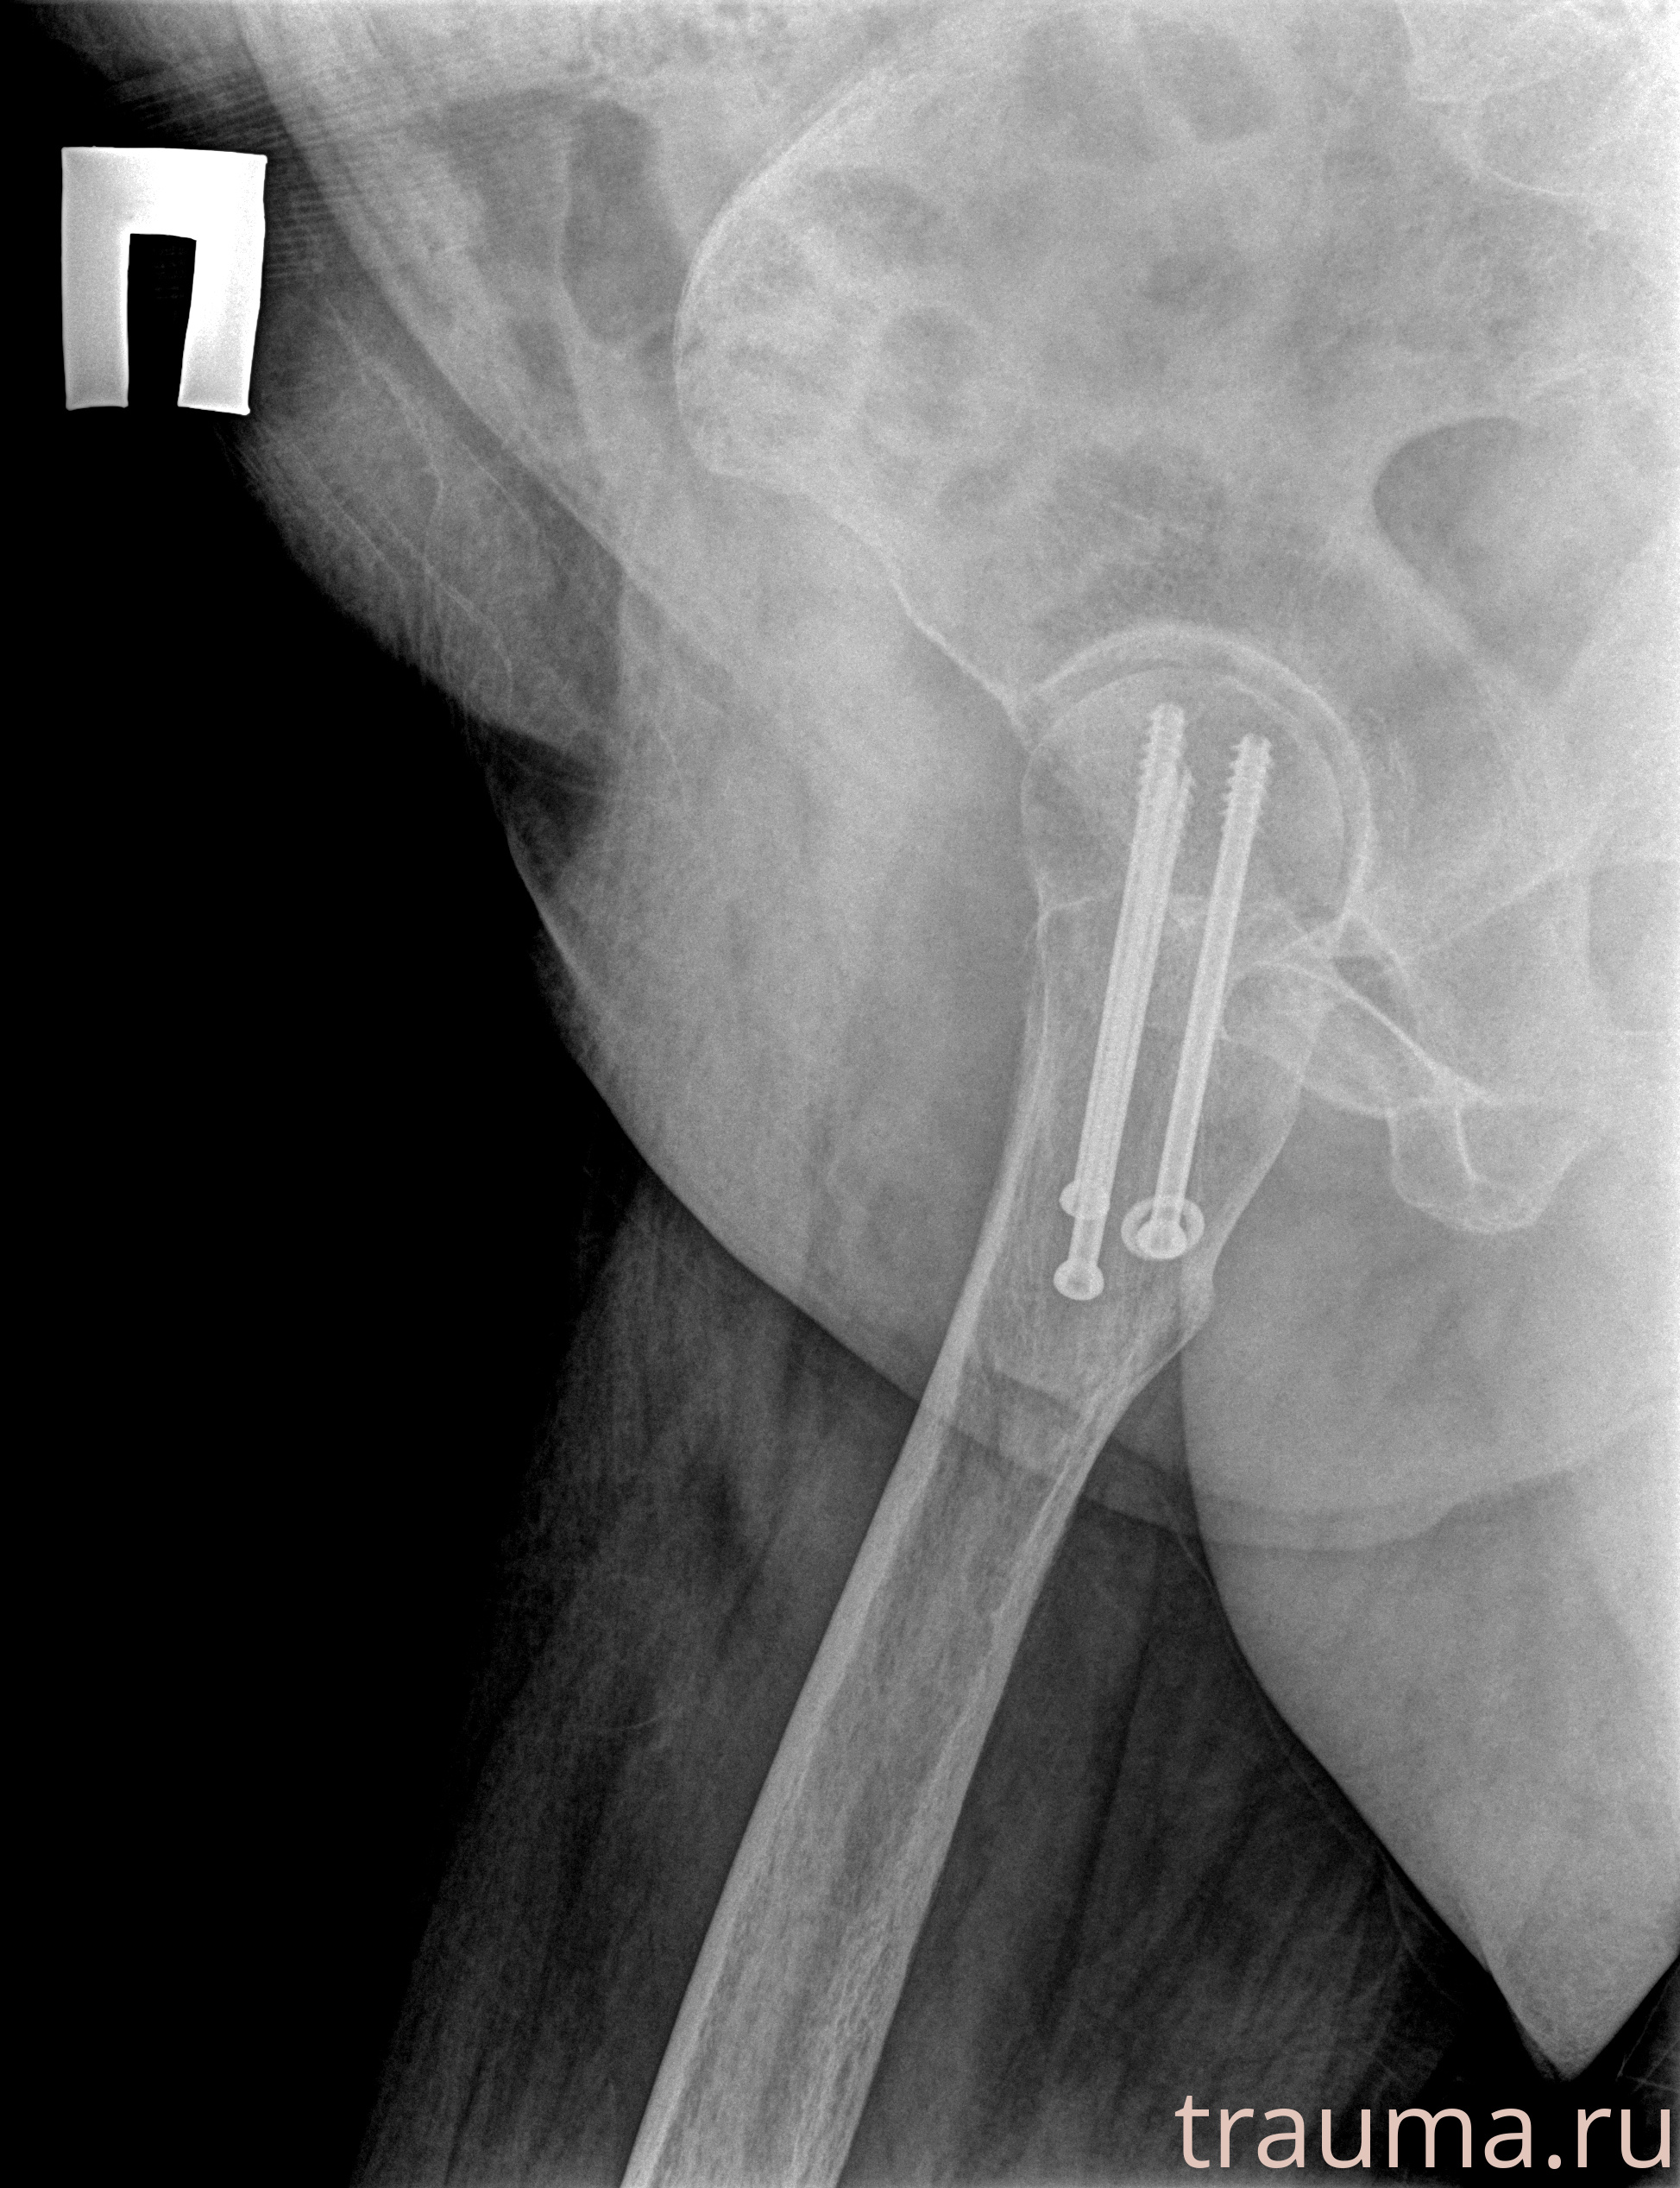

Рентгенограммы

Рентген на дому: по вашему адресу приезжает врач-рентгенолог, травматолог-ортопед с мобильным рентгеновским аппаратом, проводит диагностику травмы или заболевания, делает необходимые рентгенограммы, дает рекомендации по дальнейшему лечению. Получить качественные снимки в домашних условиях возможно благодаря уникальной методике, разработанной МосРентген Центром для института  Склифосовского